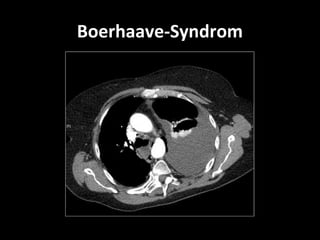

Boerhaave - Syndrom

Forciertes Erbrechen   Hermann Boerhaave 1724

Heimlich-Manöver       Männer 80%

4. – 6. Lebensdekade

Epileptischer Anfall

Plötzlicher Druckanstieg im Ösophagus

Mackler-Trias  akuter Thoraxschmerz starkes Erbrechen  subkutanem Emphysem

Forciertes Erbrechen Männer 80% Heimlich-Manöver 4. – 6. Lebensdekade Plötzlicher Druckanstieg im Ösophagus Epileptischer Anfall Heben schwerer Lasten Asthmaanfall Hustenanfall Geburt Reanimation Abdominaltrauma

Boerhaave - Syndrom ForciertesErbrechen Hermann Boerhaave 1724 Heimlich-Manöver Männer 80% 4. – 6. Lebensdekade Epileptischer Anfall Plötzlicher Druckanstieg im Ösophagus Heben schwerer Lasten Asthmaanfall Hustenanfall Geburt Reanimation Abdominaltrauma

• #57 Wegweisend für das Boerhaave-Syndrom ist das als Mackler-Trias beschriebene Bild aus starkem Erbrechen, akutem Thoraxschmerz und subkutanem Emphysem, das jedoch nur in weniger als 50% der Fälle vorhanden ist [ 1 ,  5 ,  10 ]. Der Umstand, dass zwischen dem auslösenden Ereignis und der Perforation auch mehrere Stunden liegen können [ 3 ,  5 ] und manche Patienten – so auch in unserem Fall – erst auf gezielte Nachfrage über Erbrechen berichten [ 10 ,  11 ], bereitet zusätzliche differenzialdiagnostische Schwierigkeiten.

• #58 Wegweisend für das Boerhaave-Syndrom ist das als Mackler-Trias beschriebene Bild aus starkem Erbrechen, akutem Thoraxschmerz und subkutanem Emphysem, das jedoch nur in weniger als 50% der Fälle vorhanden ist [ 1 , 5, 10]. Der Umstand, dass zwischen dem auslösenden Ereignis und der Perforation auch mehrere Stunden liegen können [3, 5] und manche Patienten – so auch in unserem Fall – erst auf gezielte Nachfrage über Erbrechen berichten [10, 11], bereitet zusätzliche differenzialdiagnostische Schwierigkeiten.

• #59 Die spontane Ösophagusruptur ist eine lebensbedrohliche Erkrankung, die seit ihrer Erstbeschreibung durch Boerhaave im Jahr 1724 bis heute häufig erst spät diagnostiziert wird [3]. Die Patienten sind zu über 80% Männer zwischen der 4. und 6. Lebensdekade [5]. Die Ursache ist ein plötzlicher Druckanstieg im Ösophagus, meist ausgelöst durch einen Brechreiz bei fehlender, gleichzeitiger Relaxation des M. cricopharyngeus [10]. Neben Erbrechen können auch ein Hustenanfall oder das Heben schwerer Lasten zur Ösophagusruptur führen

• #60 Die spontane Ösophagusruptur ist eine lebensbedrohliche Erkrankung, die seit ihrer Erstbeschreibung durch Boerhaave im Jahr 1724 bis heute häufig erst spät diagnostiziert wird [3]. Die Patienten sind zu über 80% Männer zwischen der 4. und 6. Lebensdekade [5]. Die Ursache ist ein plötzlicher Druckanstieg im Ösophagus, meist ausgelöst durch einen Brechreiz bei fehlender, gleichzeitiger Relaxation des M. cricopharyngeus [10]. Neben Erbrechen können auch ein Hustenanfall oder das Heben schwerer Lasten zur Ösophagusruptur führen